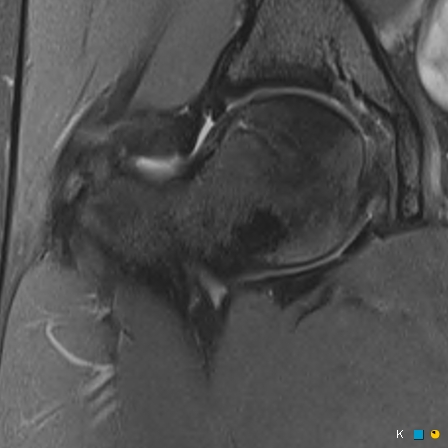

Figure 3 for case reverse slipped upper femoral epiphysis

Figure 3